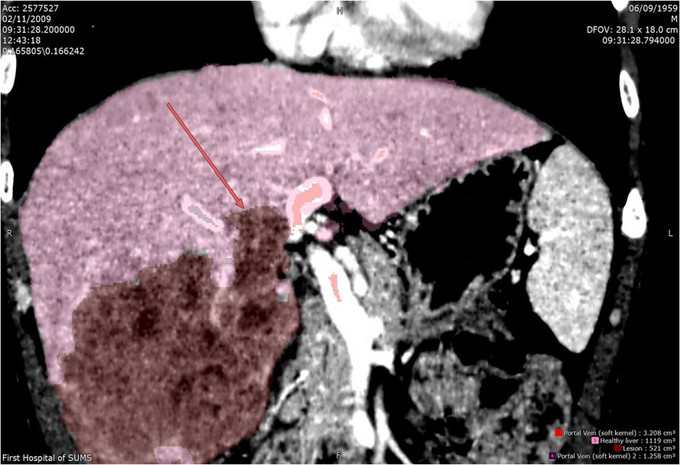

体查:未见阳性体征 实验室检查: WBC 7.24× 109/L, N 48.1%, Hb 159g/L, PLT 117× 109 /L ,PT 12.5s ; HBsAg+, HBcAb+,HBeAg+;HBV-DNA5.33× 106 IU/mL ALT 240 U/L, AST 154 U/L, ALB 36.9g/L, TBIL 13.1umol/L AFP 6270 ug/L ICG 15分钟滞留率 4.5%;Child-Pugh A级 CT提示肝S5、S6肝细胞癌并门静脉右支癌栓形成

诊断: • 肝细胞癌 • 门静脉右支癌栓 治疗:右半肝切除、门静脉取癌栓、胆囊切除术 术后病理: • 肝细胞癌,梁索型,II级,癌旁组织呈门脉性肝硬化改变 • 门静脉内组织呈现肝细胞癌改变伴坏死,符合癌栓改变